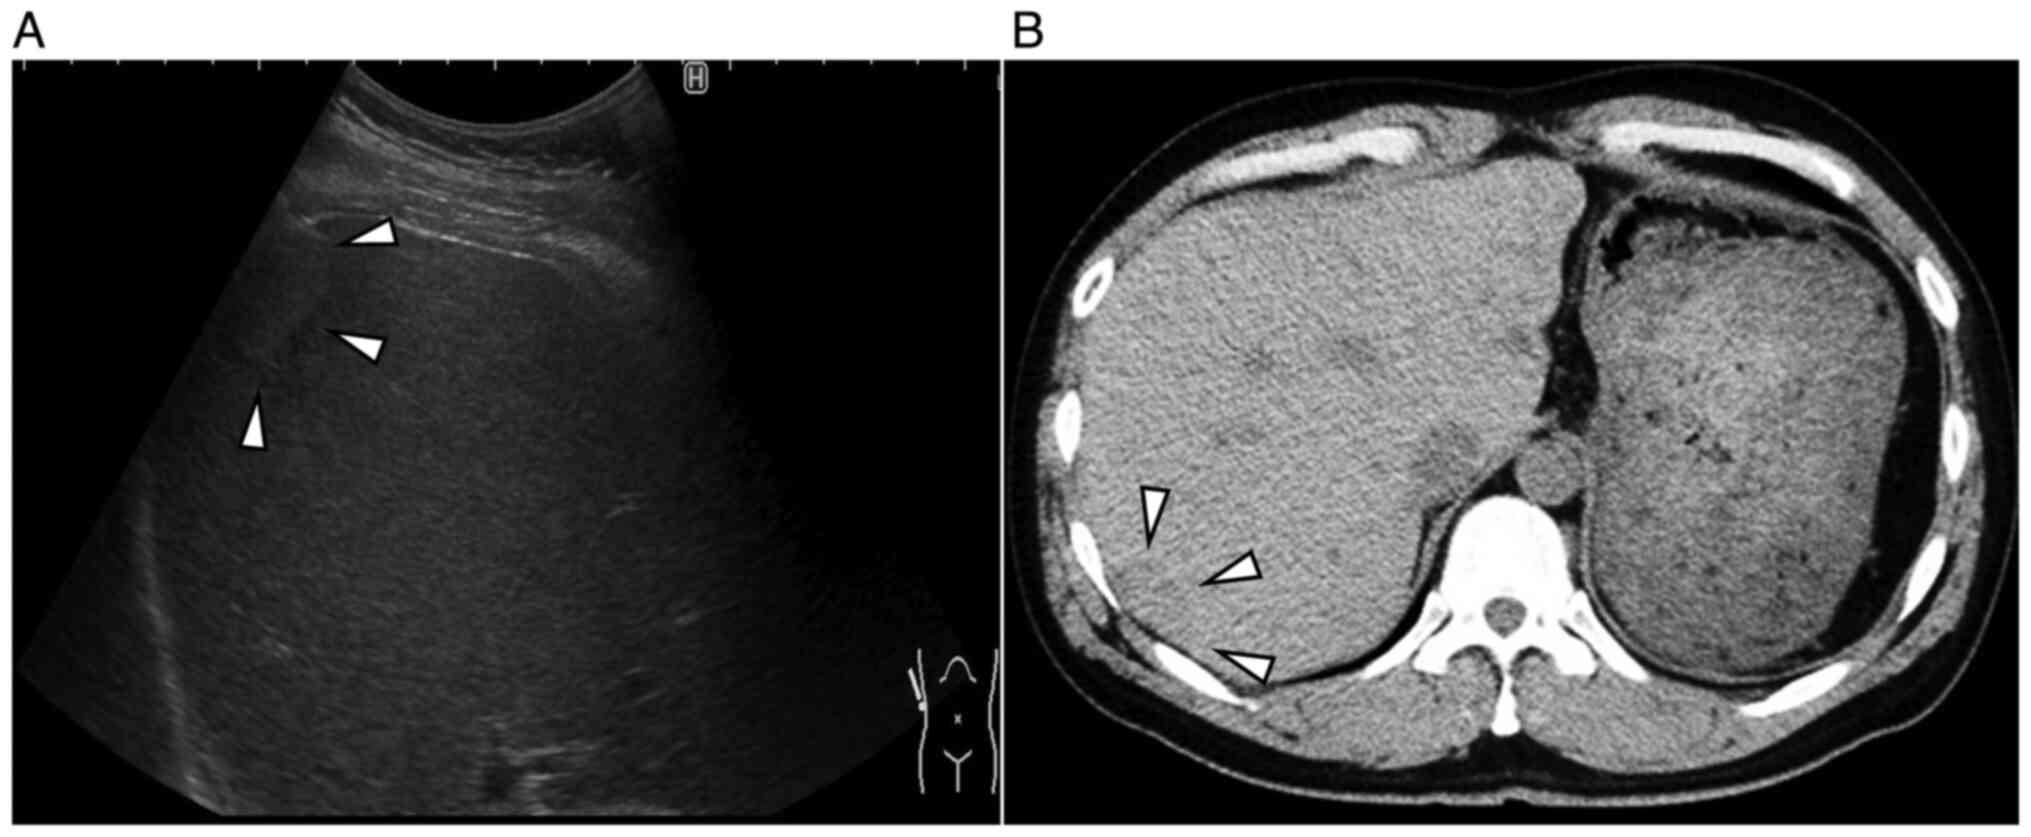

Abdominal ultrasonography (US) revealed a 2.4x1.4 cm isoechoic lesion with a hypoechoic zone at the margins in segment 7 of the right lobe of the liver (Fig. 1A). Abdominal plain-computed tomography (CT) revealed a hypodense mass measuring 2.5x1.7 cm (Fig. 1B). Abdominal magnetic resonance imaging (MRI) revealed a homogeneously hypointense mass in T1-weighted images and hyperintensity in T2-weighted images (Fig. 2A and B). The mass showed a heterogeneous hyperintensity in diffusion-weighted images and signal reduction in apparent diffusion coefficient. (Fig. 2C and D). After injecting gadoxetic acid, the lesion appeared strongly heterogeneous and hyperintense during the early phase and relatively hypointense during delayed phase that is ‘washout pattern’ (Fig. 2E and F). An indication of a pseudocapsule was also seen.

Figure 1

Abdominal ultrasonography and abdominal plain-computed tomography imaging of the IHS. (A) An abdominal ultrasonography revealed a 2.4x1.4 cm isoechoic lesion (arrows) with a hypoechoic zone at the margins in segment 7 of the liver. (B) An abdominal plane-computed tomography scan revealed a hypodense mass (arrows) measuring 2.5x1.7 cm in segment 7 of the liver.